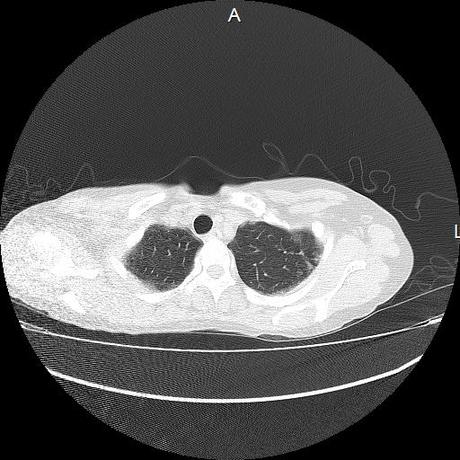

Se realiza volumen de tórax en fase simple, desde los opérculos torácicos hasta los hemidiafragmas, observándose:

El parénquima pulmonar con areas parcheadas difusas en vidrio despulido combinadas con otras areas hipodensas de baja atenuación debidas a atrapamiento aéreo y engrosamiento intersticial y zonas de fibrosis de predominio en lóbulos medios e inferiores de ambos pulmones.

- LOS HALLAZGOS PUEDEN ESTAR EN RELACIÓN A NEUMOPATIA INTERSTICIAL PROBABLE ETIOLOGIA HIPERSENSITIVA VS AUTOINMUNE/BACTERIANA/FUNGICA.